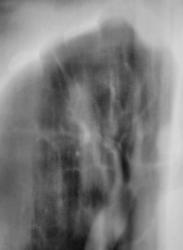

Иллюстрации 3, 4. Фрагменты изображения, полученного на CR – системе. Гомогенизация тени правого корня в области тела, измерены размеры «очагового образования» - 8 х 15 мм.